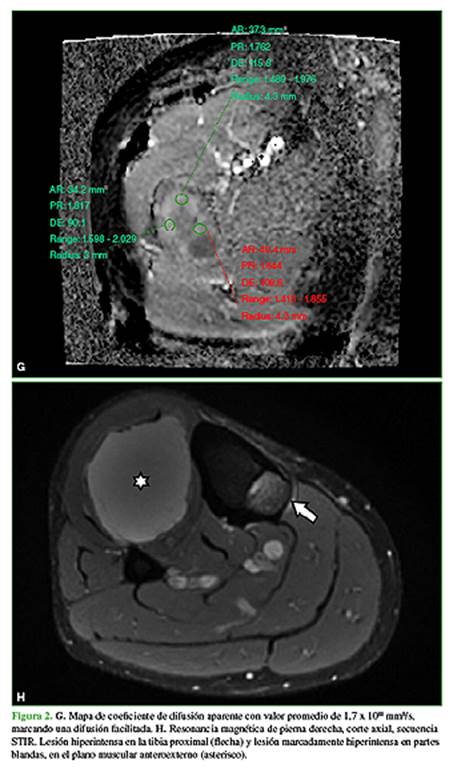

En febrero de 2020, consulta a un traumatólogo de nuestro centro. En el examen físico, la movilidad de la cadera y la rodilla es completa, sin dolor en el miembro inferior derecho. Además, se palpa una tumoración en la zona anteroexterna proximal de la pierna derecha de aproximadamente 8 cm, profunda, elástica, no dolorosa (Figura 1) que, según el paciente, tenía desde los 17 años de edad y su crecimiento era lento. Se solicitan nuevas radiografías y una resonancia magnética de cadera y pierna, y una ecografía de la masa de partes blandas en la pierna (Figura 2).

Ante la sospecha de una asociación entre lesiones óseas, interpretadas como displasia fibrosa y lesión de partes blandas, se solicita una biopsia de la masa de partes blandas (Figura 3), con confirmación histológica de mixoma intramuscular (Figura 4), que configura un síndrome de Mazabraud.

En las radiografías, se visualiza como lesiones intramedulares diafisarias, radiolúcidas, con apariencia de “vidrio esmerilado” y pérdida del patrón trabecular normal, compromiso endóstico y adelgazamiento de la cortical con áreas respetadas. Los márgenes son definidos. No se observa una reacción perióstica. Las imágenes de la tomografía computarizada confirman la presencia de lesiones homogéneas con apariencia de “vidrio esmerilado”. Puede haber áreas quísticas y calcificaciones. En la resonancia magnética, se observan lesiones con baja señal en las secuencias T1 y alta señal en las secuencias T2. Puede haber un halo hipointenso a su alrededor en las secuencias T1 y T2. Como es una lesión benigna, tiene difusión facilitada con valores de coeficiente de difusión aparente por encima de 1,1 x 10-3 mm2/s.1,2,10

Las radiografías son normales, aunque los mixomas intramusculares se pueden manifestar con calcificaciones no específicas en partes blandas. En la ecografía, los mixomas intramusculares se visualizan como masas ovoideas, poco definidas e hipoecoicas, con posibles áreas quísticas. En la tomografía computarizada, aparecen como lesiones hipointensas con pared que las separa del tejido muscular. En la resonancia magnética, se visualizan como lesiones hiperintensas en las secuencias T2, gradiente de eco o STIR. Las secuencias T1 muestran baja señal.2,6-9